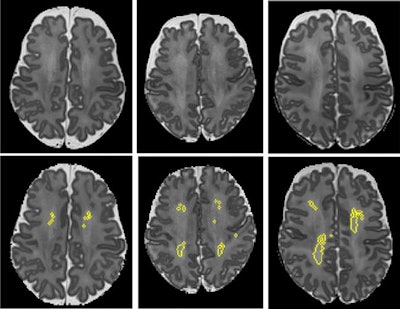

After structural brain MRI scans were performed at a term-equivalent age (mean, 40.3 weeks), the DWMA detection and segmentation algorithm was applied to the T2-weighted images. These results were also compared with visual classification of DWMA by neuroradiologists. Next, the researchers performed multivariable logistic regression analysis to assess the value of DWMA volume to predict motor development at 3 years of age.

Although visual classification of DWMA was not predictive of motor development, the software's calculation of DWMA volume was confirmed as an independent prognostic biomarker of Bayley motor scores (β = -12.59; 95% confidence interval, -18.7 to -6.48).